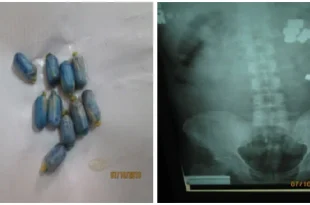

استفاده از کاربن برای پنهان کردن مواد از دید دستگاه ایکس ری

تلاش برای جلوگیری از شناسایی مواد از طریق دستگاه بازرسی ایکس ری توسط راهکارهای مختلف، تنها منجر به ایجاد سایه‌ای روی نمایشگر دستگاه شده و باعث ایجاد شک می‌شود. هر تلاشی،مانند استفاده از سرب یا کاربن یا هر چیز دیگری، فوراً روی تصویر علامتی ایجاد می‌کند که جستجوی بسیار دقیق …